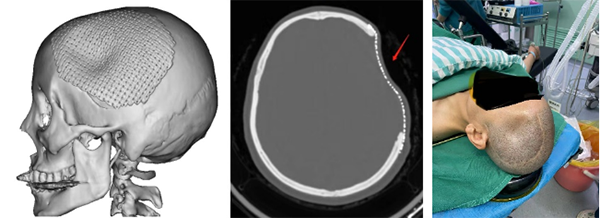

患者钛网颅骨修补后外伤致钛网凹陷

入院后,穆苍山为患者制定了完善的翻修手术方案。通过3D打印技术,个性化定制PEEK外形,完善术前检查,耐心向患者家属解释手术治疗方案和PEEK设计过程,以及手术后注意事项。得到患者和家属同意后,神经外十科团队在全麻下为患者行原钛网取出同时PEEK翻修手术。术后,患者恢复顺利,1周后拆线回家休息。